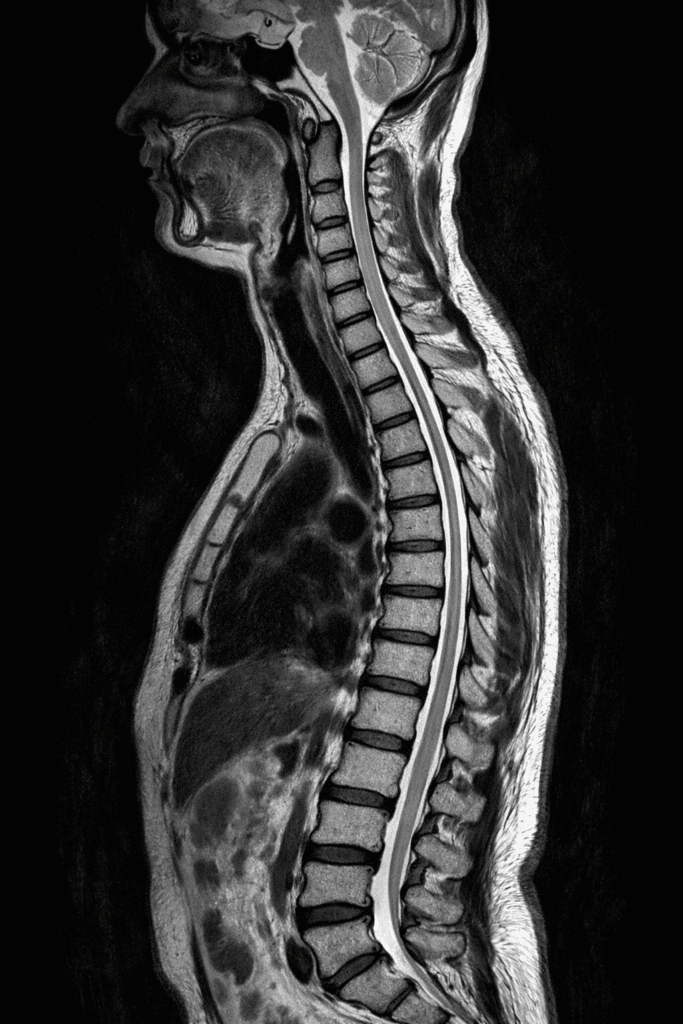

The spinal cord and vertebrae are examined using MRI spine scans. There are three main types:

This scan helps detect: Slip disc (herniated disc), Nerve compression, Spinal injuries and chronic back pain.